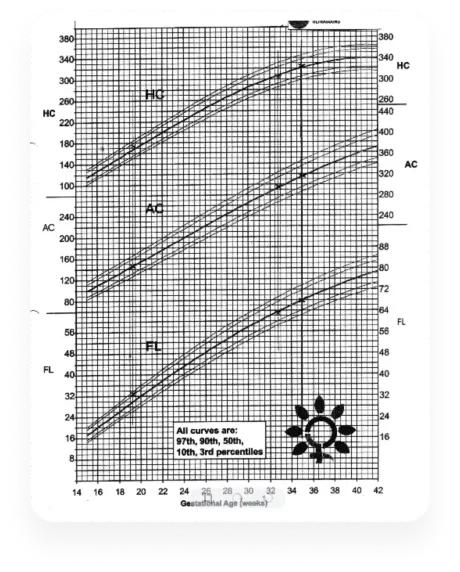

Document accessibility

Provide a platform for sharing supplementary documents like growth charts or blood reports, making them readily available on the portal.